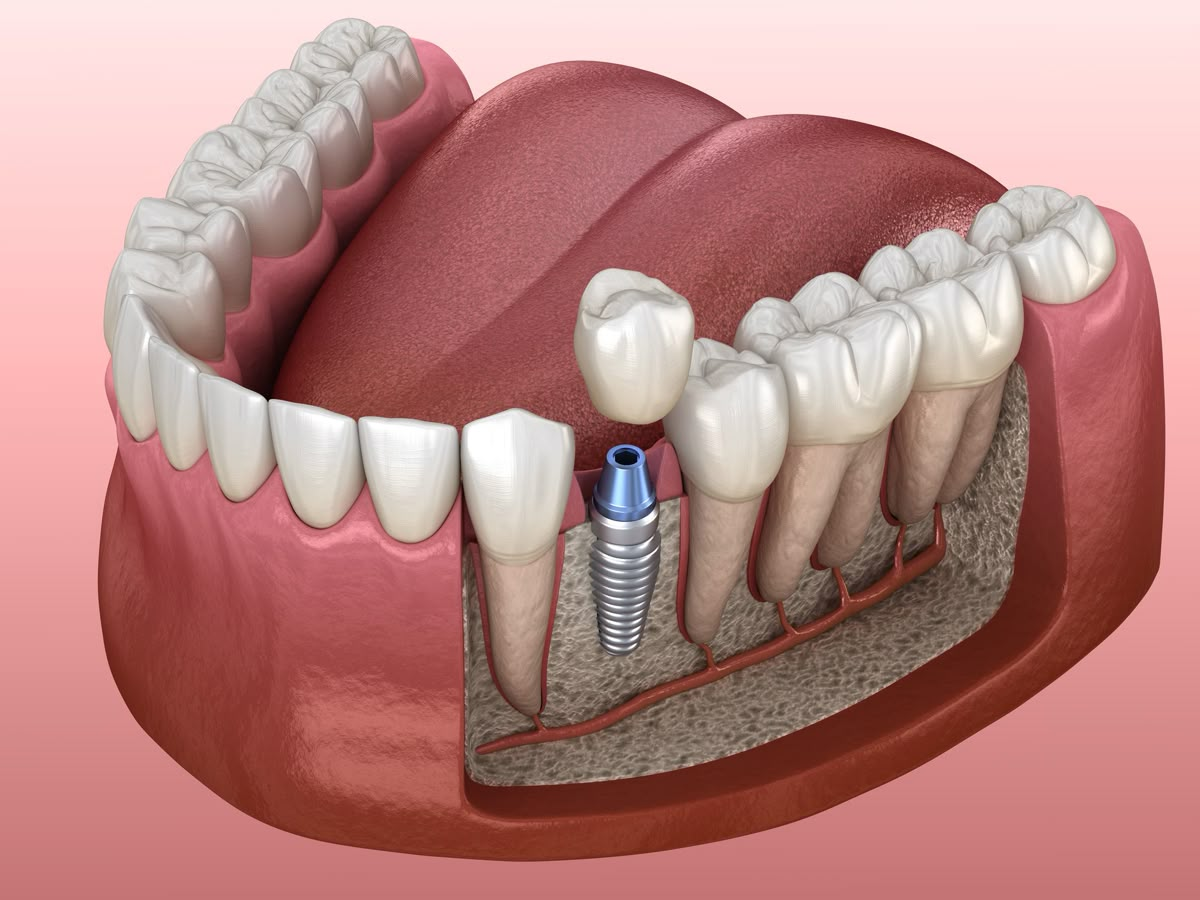

O implante é um “parafuso” de titânio colocado dentro do osso para substituir a raiz do dente perdido. Ele serve como base para fixar uma prótese que parece e funciona como um dente natural.

Existem soluções como enxerto ósseo, levantamento de seio e implantes curtos. Cada caso é avaliado individualmente para definir a melhor opção.